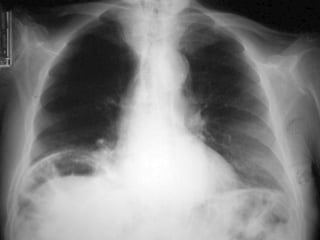

- Khung xương, đáy phổi

Phân tích hệthống: - Khí tự do trong phúc mạc - Khí trong ống tiêu hóa: hình thái - Đánh giá thành ruột - Tụ khí ngoài phúc mạc? - Khí trong các cấu trúc ống khác - Hình ảnh các cấu trúc mô mềm sinh lý - Tụ dịch trong phúc mạc - Các bóng mờ bệnh lý - Các đóng vôi bệnh lý - Khung xương, đáy phổi